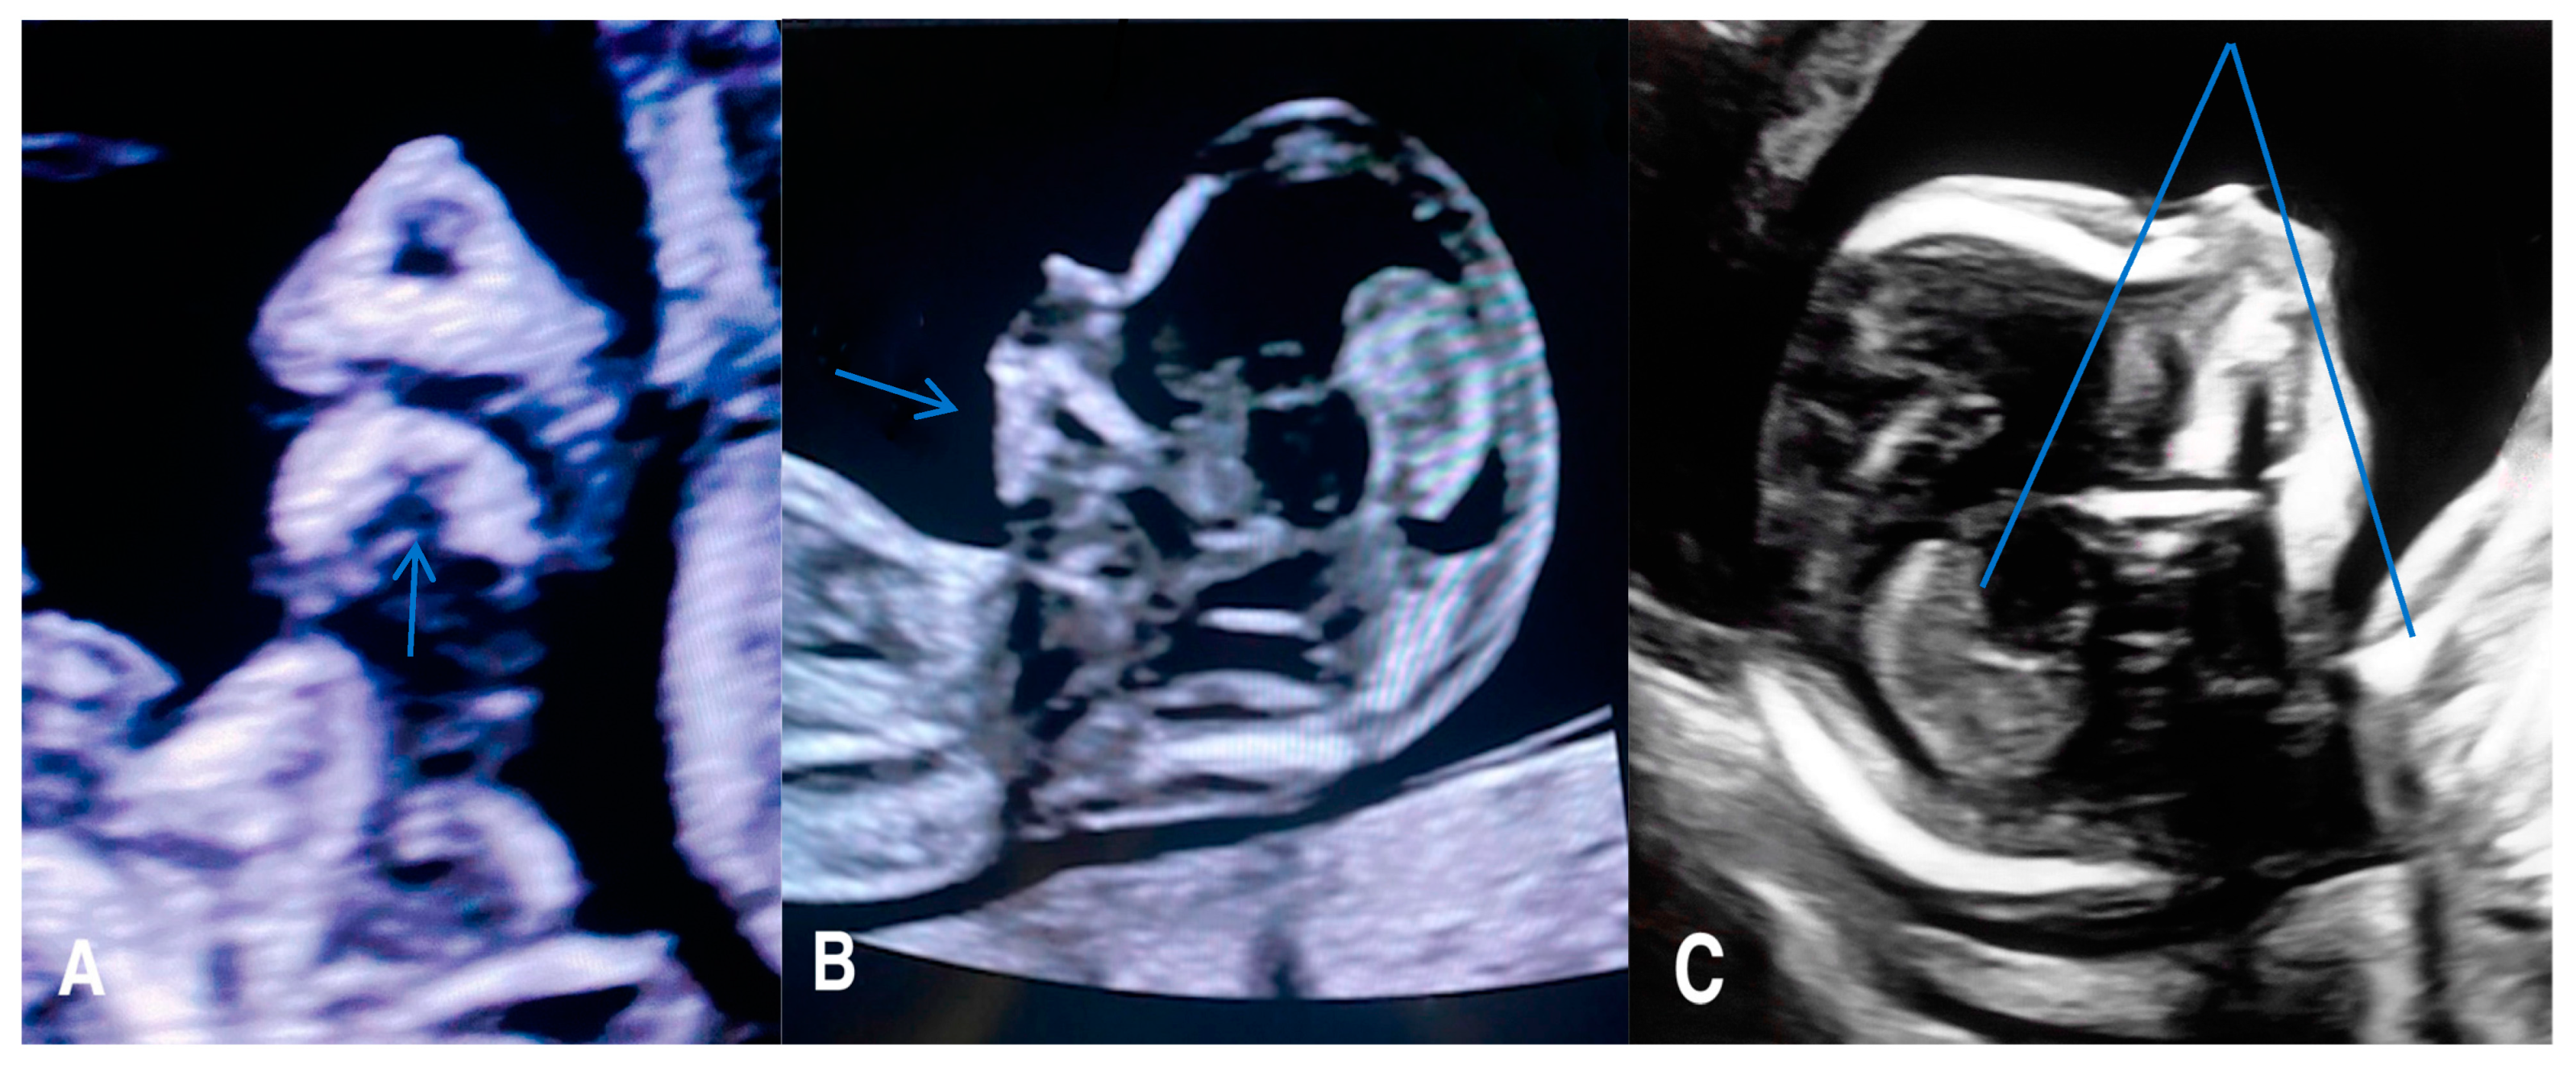

Facial clefts include a wide variety of pathologies that result from the failure of fusion in the facial area during the early embryonic/fetal period, leading to a gap in the fetal face [20]. These clefts can affect the lip, philtrum, alveolus, and hard and soft palate to varying degrees. Facial clefts may be typical or atypical (Figure 1).

Figure 1.

(A) Axial view of a 21 week old fetus with unilateral left cleft lip, cleft palate, and premaxillary protrusion (B) A 3D surface rendered image of the same fetus with unilateral left cleft lip and cleft palate. (C) A 3D surface rendered image of a 16 week old fetus with isolated left unilateral cleft lip.